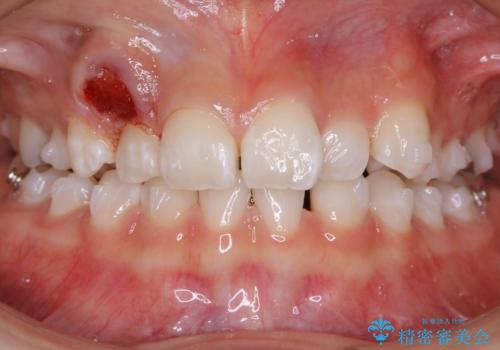

- 歯のガタつきを主訴にご来院されました。

ガタつきがあるだけでなく、元々永久歯が欠損している「先天欠如」で歯の本数が少なく噛み合わせ等も治療する必要がありました。

かなり特殊な状況からの矯正治療になるため抜歯する本数や位置、並んだあとのスペースのコントロールを慎重に計画し、マウスピース装置のインビザラインで治療を開始しました。